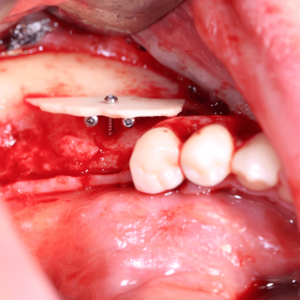

Eine erfolgreiche Regeneration von Hart- und Weichgewebe ist essenziell für die langfristige Stabilität und Ästhetik von Implantaten. In der modernen Zahnmedizin existieren dafür vielfältige innovative Techniken, die gezielt auf die individuellen Bedürfnisse des Patienten abgestimmt werden können. Um genau diese Techniken geht es bei dieser Fortbildung! Die Referentin Dr. Dr. Diana Heimes vermittelt Ihnen in ihrem Vortrag die

neuesten Erkenntnisse und Techniken der Hart- und Weichgeweberegeneration. Sie erhalten fundierte Einblicke in die Anwendung verschiedener Biomaterialien. Zudem profitieren Sie von den Fallbeispielen der Referentin.

Sie lernen Schritt für Schritt die Vor- und Nachteile der Schalenaugmentation unter Nutzung allogener Knochen-ersatzmaterialien kennen. Auch hier zeigt Ihnen die Referentin Dr. Dr. Heimes praxisnahe Anwendungsbeispiele. Im Anschluss bleibt genügend Raum für Ihre Fragen.